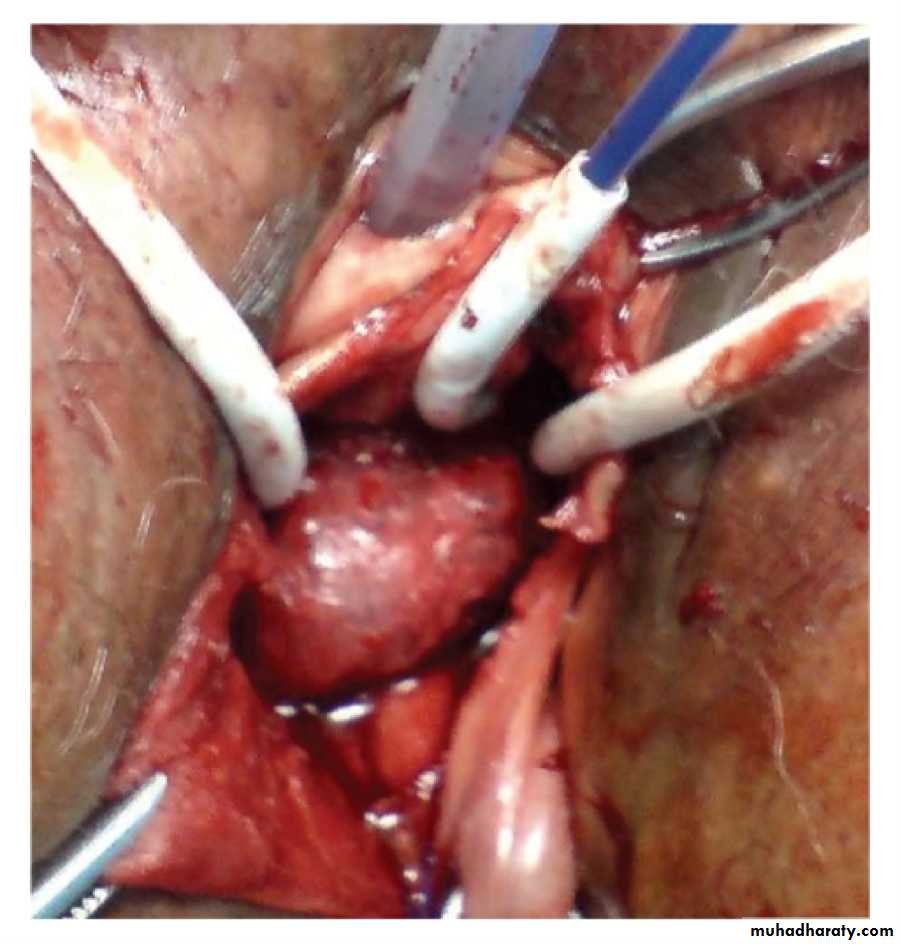

Colposuspension operation is associated with highest success rate95% at one year.

It is effective operation for stress incontinence.Retropubic procedures — The Burch colposuspension and the Marshall-Marchetti-Krantz (MMK) procedure are the two most common retropubic operations for SUI. In the Burch procedure, the endopelvic fascia adjacent to the mid and proximal urethra at the bladder neck is attached to the pectineal (Cooper's) ligaments on the posterior surface of the superior pubic ramus. The MMK procedure attaches the endopelvic fascia next to the bladder neck to the periosteum of the posterior pubic symphysis.

The Burch procedure can be performed by laparotomy or laparoscopically.

Complications of the Burch procedure include:

Urinary retention Detrusor over activity Injury to the bladder or ureter Infection Hemorrhage, Enterocele.Laparoscopic Colposuspension of the bladder neck is gaining popularity. Pereyra or stamey.